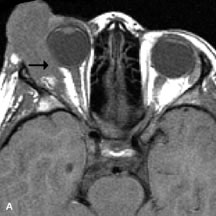

Extraocular muscle enlargement in patients with thyroid-associated orbitopathy is demonstrated equally well with CT and MRI studies. However, the superior tissue contrast on MR images reveals better details of the relationships of the optic nerve to the thickened muscles at the orbital apex (Fig. 16).50 In addition, MRI may be able to differentiate between muscles that are enlarged as a result of edema and active inflammation and those enlarged because of fibrosis by their T2 relaxation times.21 Quantitative MRI was not found to be accurate in predicting the success of low-dose orbital irradiation.51 However, a muscular index relating the diameters of the rectus muscles to the bony orbital dimensions was useful in predicting optic nerve compression.52

Fig. 16. A-C, T1-weighted MR scans obtained with a high-resolution surface coil demonstrate fusiform enlargement of the extraocular muscles. The medial, lateral, and inferior rectus muscles are especially involved. Note the relative sparing of the tendinous insertions, a finding characteristic of this disease process, as well as fatty infiltration of the lateral and inferior rectus muscles. There is marked proptosis, best visualized on the sagittal image (A), and mild crowding of the optic nerve at the orbital apex.